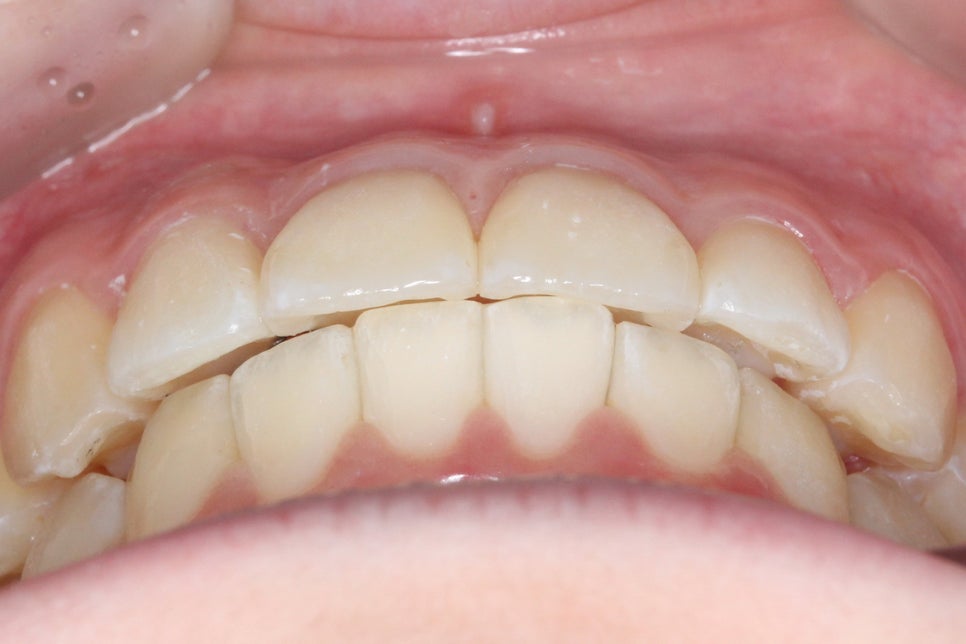

송곳니덧니 교정 Case로 구내사진을 보시면

사진 상으로 좌측 송곳니가 위쪽으로

변위되어 있는 모습을 확인할 수 있습니다.

다음으로 overbite 사진입니다.

전치부가 교합된 모습을 보면

상악에 비해 하악의 crowding이

심한 모습을 확인할 수 있는데요,

아랫니가 배열된 각도가 앞뒤로 심하게

삐뚤거리는 모습으로 이러한 경우

송곳니덧니 교정 후 전치부의 모습입니다.

치료전과 비교해보면 송곳니의 높이가

확연하게 달라진 것을 확인할 수 있는데요,

high canine로 인해 비교적 높은 위치에

맹출되어 있던 견치가 주변 치아들과

조화로운 위치로 교정된 모습입니다.

overbite 모습 역시 교정 후 아랫니가

가지런해지면서 전치부의 crowding이

해소된 모습을 확인할 수 있습니다.

deep bite나 open bite 증상 없이

바르게 교합되는 전치부의 모습이네요^^

2mm정도 덮는 상태가 이상적인 모습입니다.